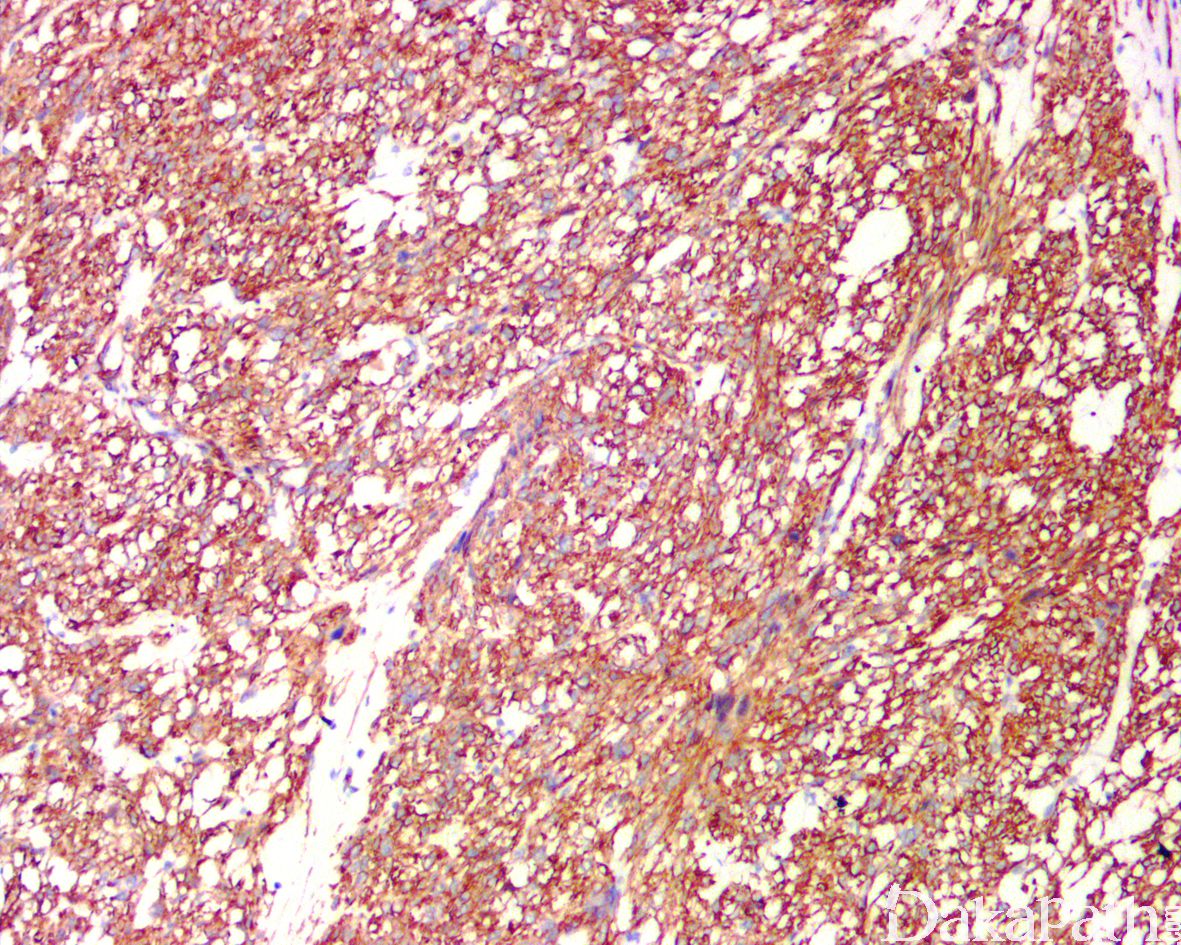

免疫组织化学染色:

SMA、caldesmon、desmin、calponin、P16 常阳性,ER、PR、S100. myogenin、myoD1. EMA 及广谱 CK 常阴性(具有上皮样分化特征的平滑肌肉瘤可局灶表达 CK)。